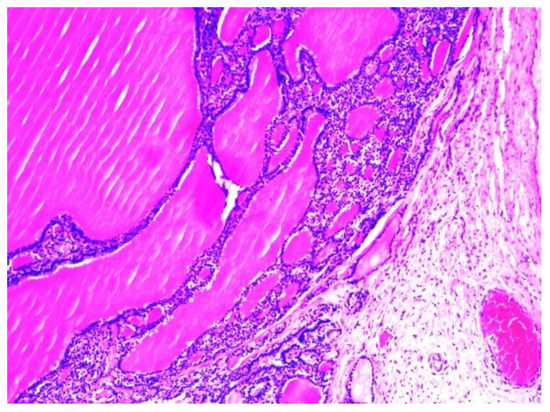

The histopathological examination of the multilocular cystic mass was consistent with benign SO, as its walls were composed of mature thyroid tissue without architectural or cytological atypia, with variable-sized follicles containing eosinophilic colloid (Figure 6). The stroma between the follicles was fibrous with focal extracellular cholesterol deposits. The largest cyst was lined withflat epithelium, with some thyroid follicles in the fibrous walls. The content of some small cysts was represented by purulent exudate (Figure 7). No other epithelia were detected.

Figure 6. Histopathological aspect of the cystic wall, with variable-sized mature thyroid follicles filled with colloid (H&E stain, magnification: 100×).